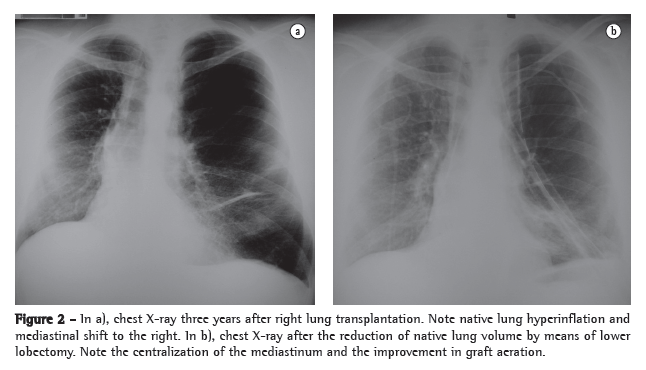

Three years after transplantation, there was progressive deterioration of pulmonary function, with clear signs of lung hyperinflation (FEV1, 69%; FVC, 71%; TLC, 136%; and RV, 278%). At the time, the patient experienced dyspnea on minimal exertion.

Reduction of native lung volume by means of left lower lobectomy was chosen because scintigraphy revealed lower perfusion in the left lung base (22%) than in the right lung base (78%). In addition, we considered the lower likelihood of prolonged air leak related to lobectomy. The patient underwent lobectomy. There was a favorable response and immediate improvement in the breathing pattern. Postoperative pulmonary function testing showed an FEV1 of 81%, FVC of 76%, TLC of 99% and RV of 150%. Four years after surgery, the patient was in good health and was fully able to perform his habitual activities (Figure 2).